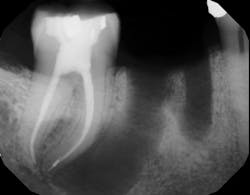

- The type of endodontic treatment dictates the length of healing. Nonsurgical endodontic treatment has a usual healing time of three months. Surgical intervention such as an apicoectomy due to large lesion size can take six to 12 months to heal (figures 1 and 2).

If definitive crown placement is delayed and the patient has excessive forces on the tooth or suffers from direct trauma, the tooth can fracture. In many cases, a decision must be made upon full bone healing versus the likelihood of crown fracture (figure 3–6). In addition, most studies show that full-coverage crowns are a main factor in determining long-term success of root canal therapy, with successes ranging from 92% for teeth receiving crowns compared to 35% for those not receiving crowns after a one- to five-year follow-up.2 In another study on molar teeth five years after root canal therapy, teeth that had crowns placed had a success rate of 78% versus 36% without crown coverage.3